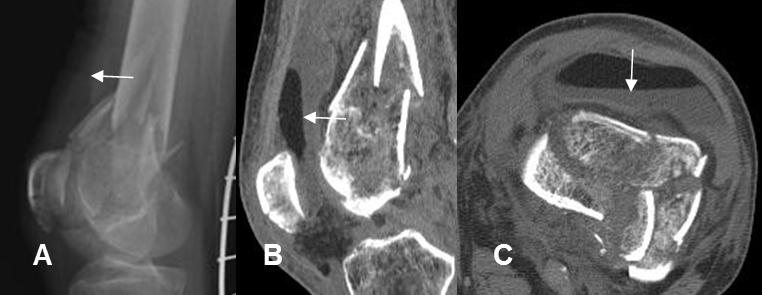

Fig 56 B. Lipoartrosis.

A: Rx lateral. Fractura conminuta del fémur distal. Se visualiza en cojinete graso a nivel suprapatelar, por derrame articular.

B: TAC reconstrucción sagital y C: TAC axial. Nivel grasa/líquido intra-articular, que indica lipoartrosis.